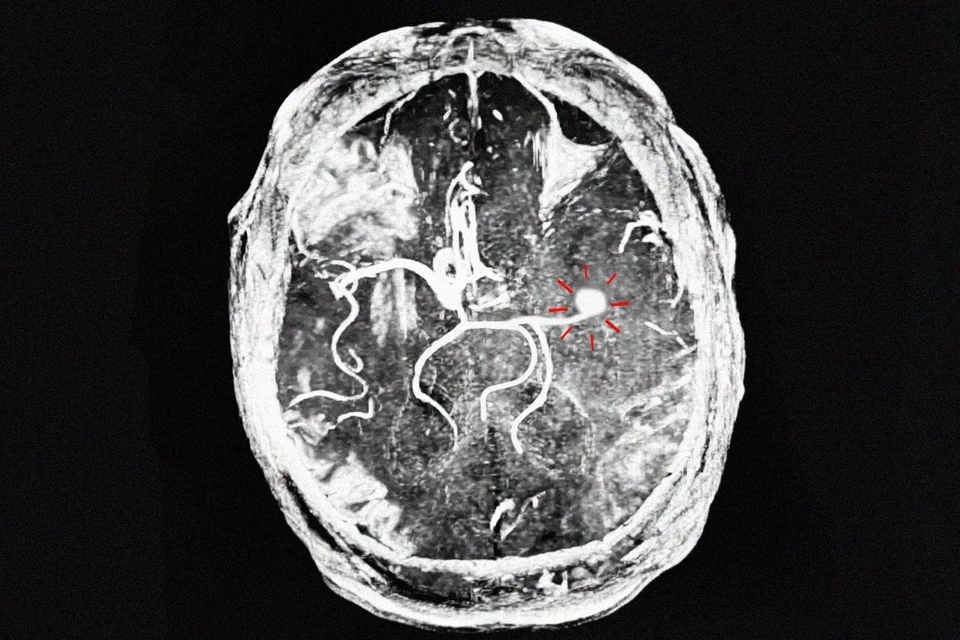

Врачи Областной клинической больнице рязанцу помогли перенести инсульт без серьезных последствий. Залогом эффективного лечения стала оперативность - госпитализация прошла в пределах «терапевтического окна», то есть в первые часы после появления симптомов.

Мужчине стало плохо на улице, и, к счастью, нашлись неравнодушные прохожие, которые сразу же вызвали скорую помощь. Когда пациент поступил ОКБ, ему после осмотра провели тромболитическую терапию (тромболизис) — это растворение тромба специальным препаратом. В итоге повреждения мозга удалось избежать.

«Тромболизис проводится исключительно в стационаре в первые 3–4,5 часа после появления симптомов инсульта», — рассказал заведующий отделением для больных с острым нарушением мозгового кровообращения Олег Сорокин.